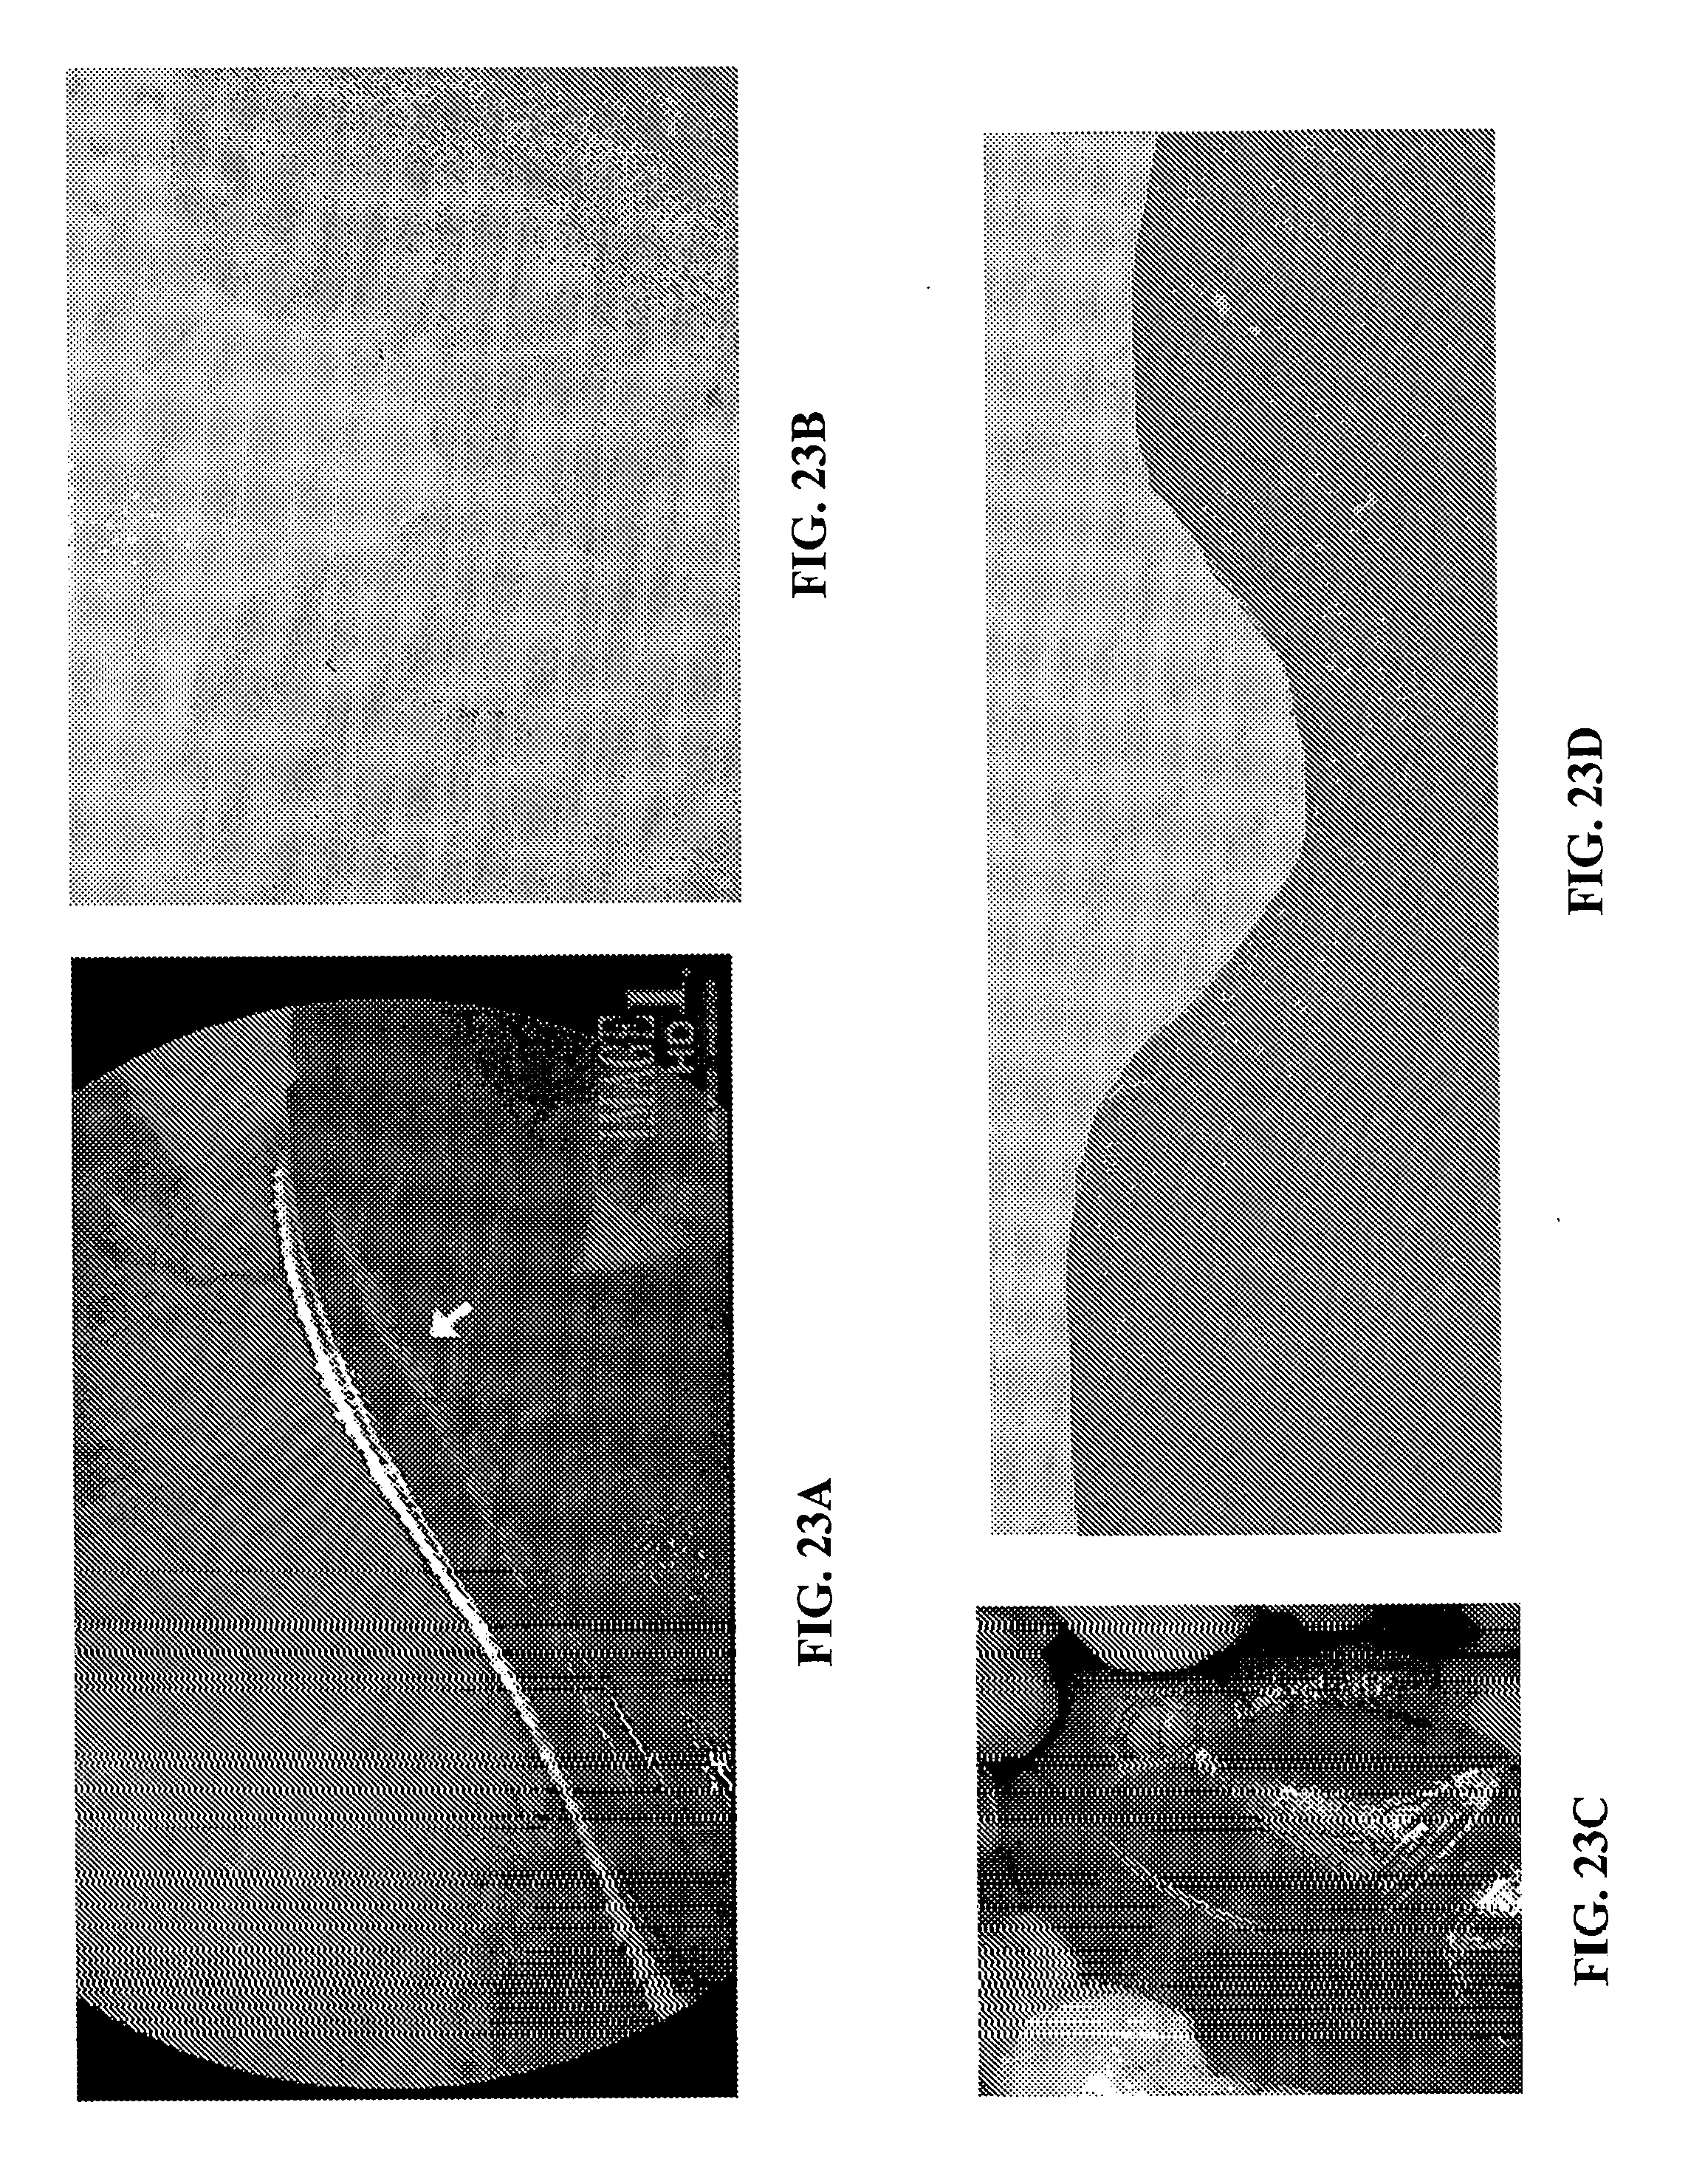

[0043]

FIGS. 23A-D are images relating to the TRAFFIC system described herein which, when placed cranial to the liver in a dog, the TRAFFIC system made an indentation on the liver. Liver parenchyma deep to the indentation was completely normal, suggesting that the TRAFFIC system was bio-inert.